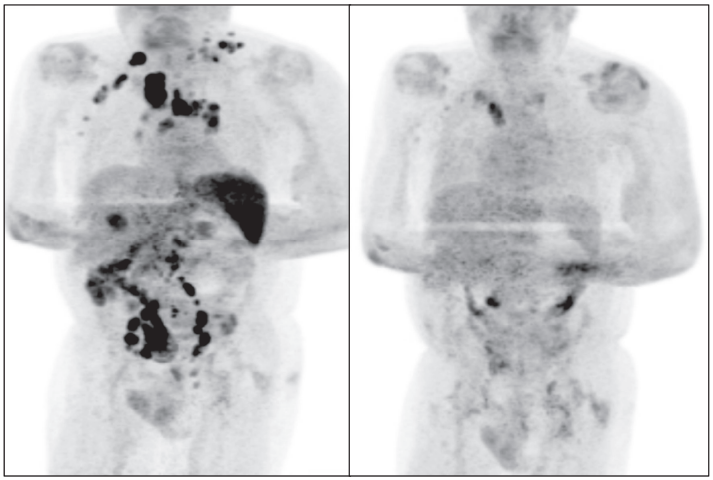

患者鎖骨上淋巴結(jié)的活檢顯示,EBV陽(yáng)性(EBV病毒聚合酶鏈反應(yīng)(PCR)4800拷貝/毫升)。確診為霍奇金淋巴瘤,F(xiàn)DG-PET / CT顯示其處于疾病晚期階段。

四個(gè)月后,患者身上可觸及的淋巴結(jié)腫大有所減輕少,臨時(shí)PET / CT掃描顯示淋巴結(jié)病的廣泛消退。EBV病毒PCR也降至413拷貝/ ml(log 10 2·62)。

左圖為最初的PET/CT掃描結(jié)果,右圖為4個(gè)月后的PET/CT掃描結(jié)果